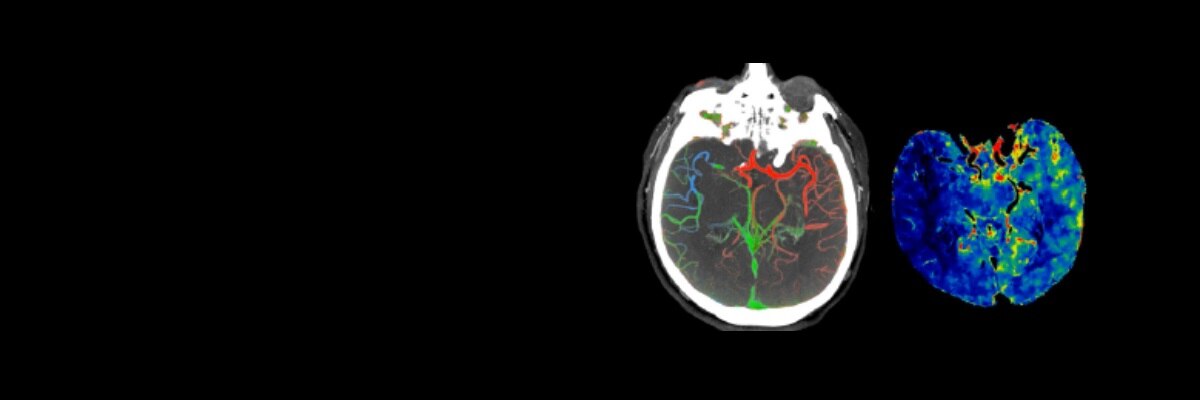

A patient with suspected TIA or stroke will typically receive a general and neurological examination followed by diagnostic brain imaging, performed immediately on arrival so that treatment can be started promptly.3 Optimal scanning coupled with workflow applications and protocols designed for stroke help deliver accurate and quick diagnosis to impact patient outcomes.

Revolution brand of CT systems

Capable of acquiring neuro perfusion and CTA of the brain in a single exam to enable comprehensive functional and anatomical assessment.

FastStroke CT Application

Simplifies and organizes CT images for fast evaluation of Stroke patients.

5-minute brain with HyperWorks

Providing structural as well as vascular information with improved resolution and precise characterization in 5 minutes.